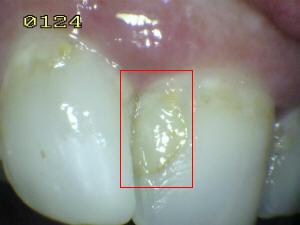

Sistema Internacional para la Detección y Evaluación de Caries (ICDAS)

¿Determine los códigos pertinentes a cada imagen?

Click en el hipervínculo: Para comparar el resultado de su diagnóstico